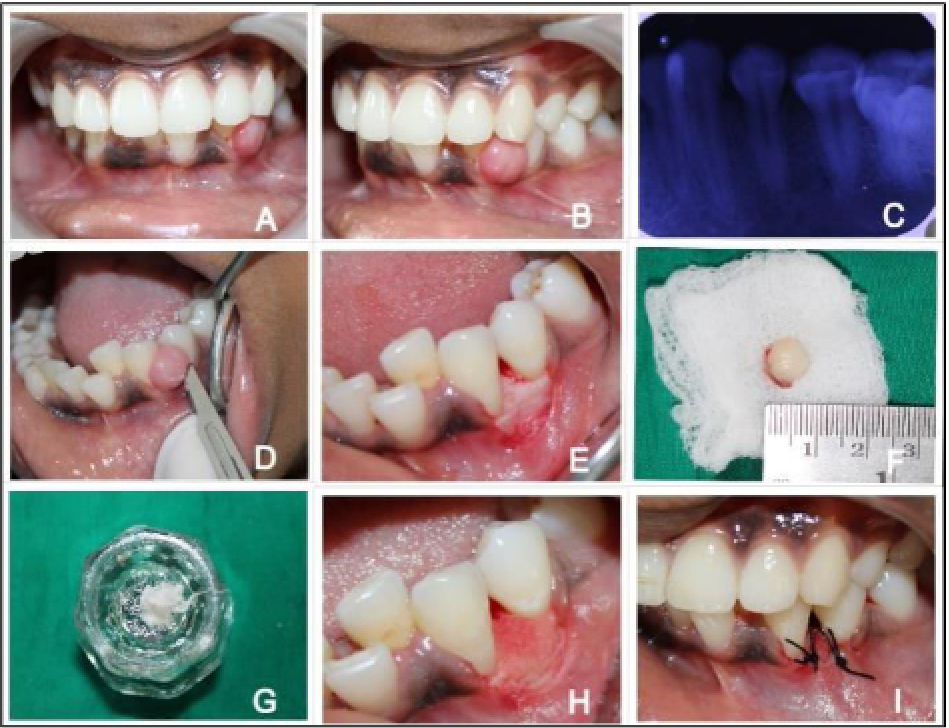

Management of Mucosal Fenestration and Palatogingival Groove (2015)